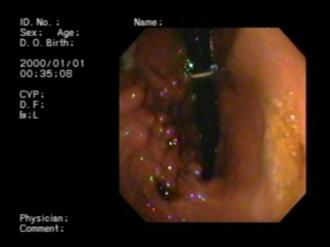

検査にあたり、事前に説明を受け、高価な金額の内容も丁寧に説明され、不安を与えない配慮がなされていることに、信頼できると思いお任せすることに決めました。6月8日、胃カメラ、血液検査、アレルギー検査など色々としていただき、先生の指示を守りました。また、食事方法が360度変更され、当初は戸惑いも有り不安が無いとは言えませんでした。結果が届くまで、吐く症状は変わらず心配で仕方がありませんでした。しかし、診断後に薬を戴いてから(11日経過)は、一切吐かない日が続いています。